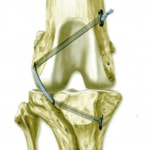

タイトロープ法

タイトロープ法は人工靭帯を用いて膝関節の安定化させる関節外固定法の一つです。大腿骨遠位・脛骨近位にドリルで穴を開け、Tight Ropeと呼ばれる人工繊維を通し固定します。従来の方法に比べて等尺点(isometric point)を保つ位置に人工靭帯を設置することができる為に、人工靭帯の緩みが最小に抑えられ膝関節がより安定化されると報告されています。